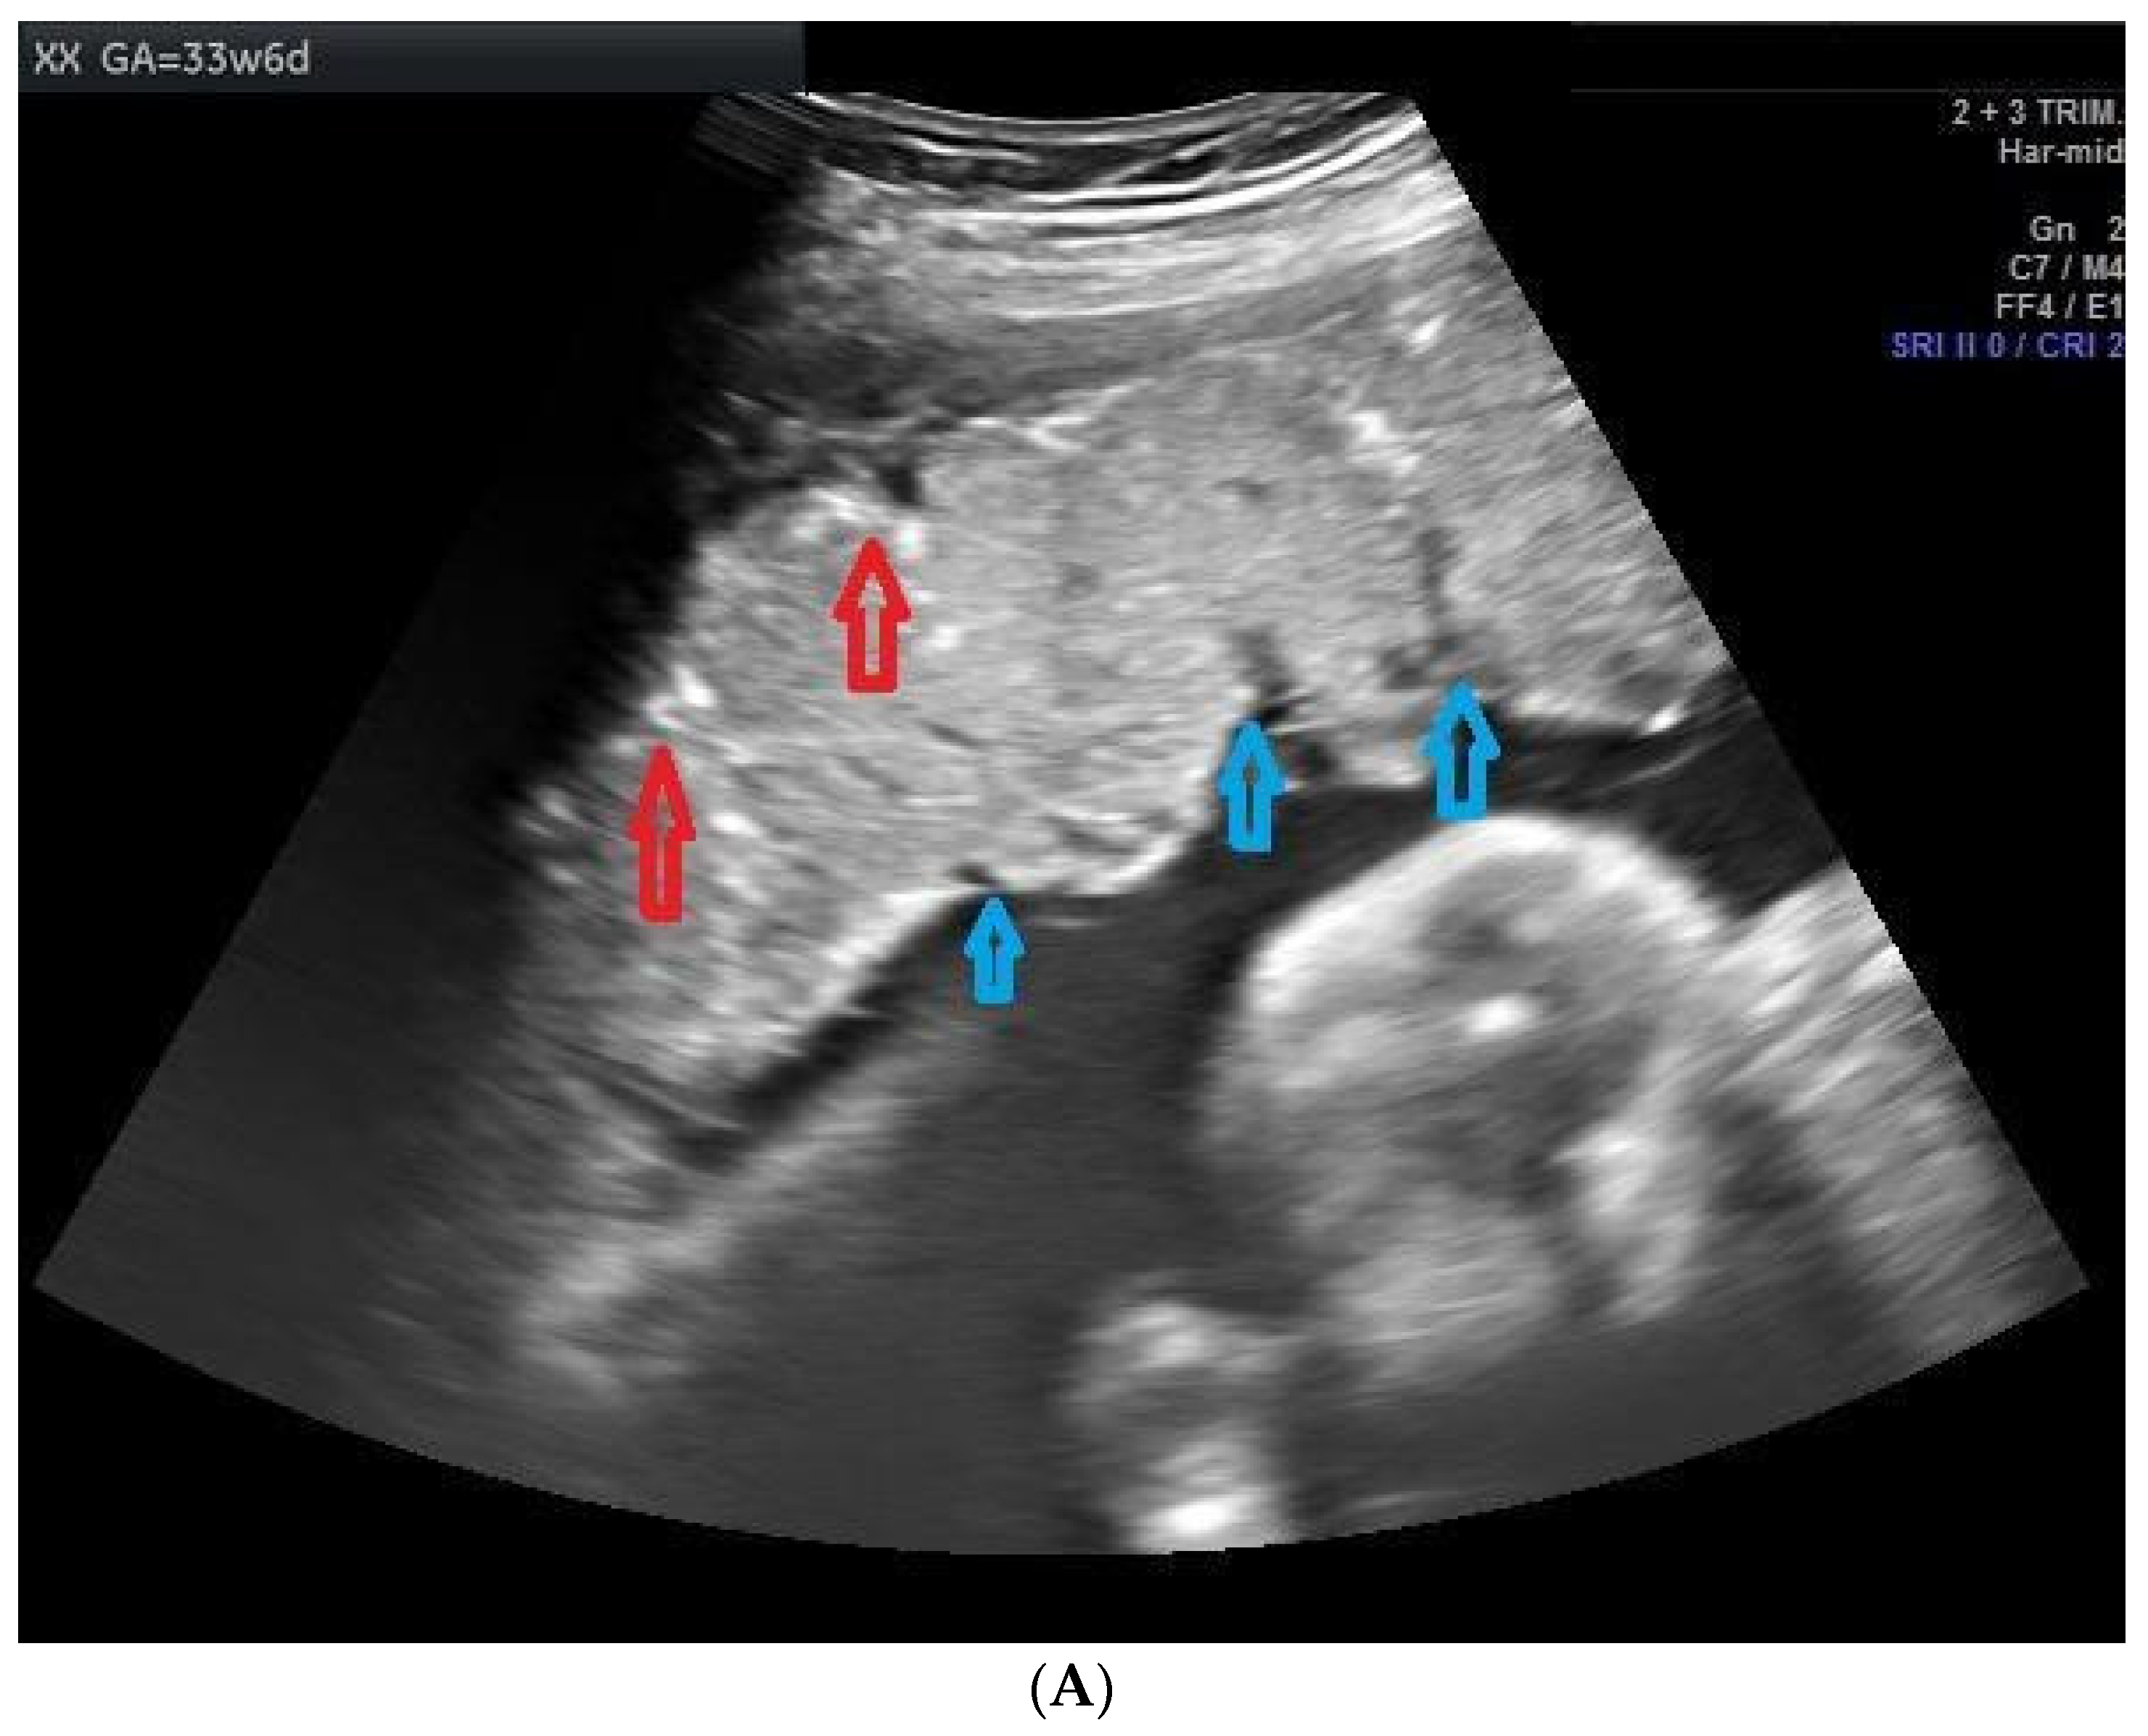

Ultrasound was performed to document the cases of PPC from 28 weeks of gestation at every four-week interval. Echogenic indentation from the chorionic plate to the basal layer dividing the placenta into random lobules, similar to cotyledons, was considered Grade III placental calcification (Figure 2A,B). A doppler flow study was conducted starting from 32 weeks of gestation to 36 weeks at an interval of 4 weeks. The ultrasound equipment used for this study was a Siemens Acuson × 300 PE USG machine with a curvilinear transducer and a frequency of 1.9 to 6.4 MHz, analyzed by a single consultant in order to avoid interobserver bias. The images were verified by another senior consultant to ensure the accuracy of diagnosis. Both the consultants were obstetricians trained in ultrasonography. In the umbilical artery Doppler study, absent or reversed end-diastolic velocity (AREDV) was considered to reflect poor uteroplacental blood flow. The other Doppler indices measured were the umbilical artery pulsatility index (Umb PI) ≥ 95th, middle cerebral artery pulsatility index (MCA PI ≤ 5th), cerebro placental ratio (CPR ≤ 5th), Mean uterine PI ≥ 95th, and unilateral or bilateral notch in the uterine artery.

Figure 2.

(A) Image showing placental calcification and lobulation (grade 3 placenta) in a case of 26-year-old primigravida at a gestational age of 33 weeks and 6 days. Red arrows show the placental calcification and blue arrows show lobulations. (B) Image showing grade 3 placental calcification in a 31-year-old primigravida at a gestational age of 35 weeks and 1 day. Red arrows show the placental calcification.